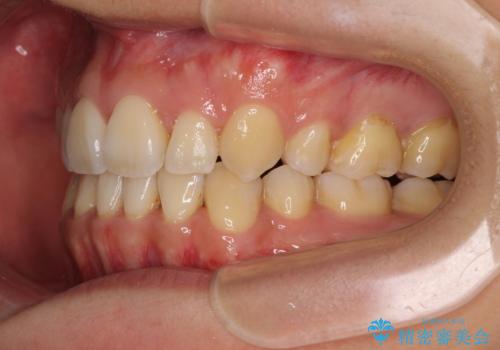

元の歯列が想像できないほど、きれいな歯列に整えることができました。

第二小臼歯抜歯の矯正治療は、治療期間が長引くことが多いですが、動きが非常に良く、予定の治療期間で終えることができました。